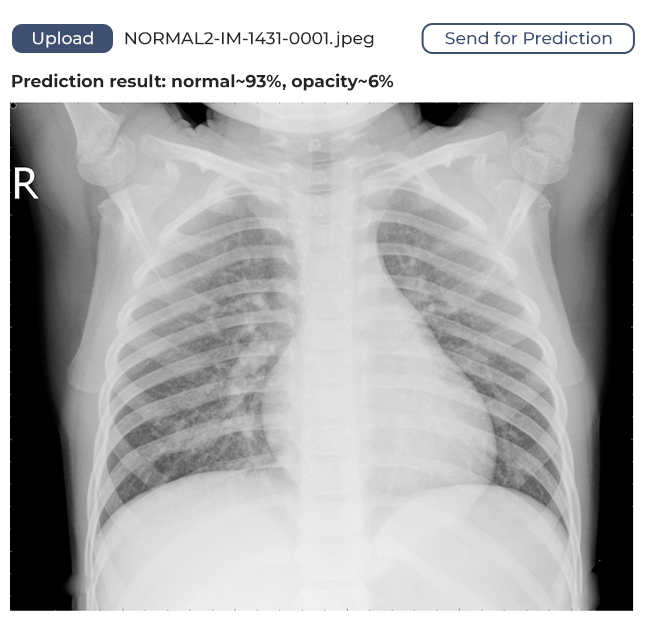

The model we’ve developed has a margin of confidence and uses binary identification. What does this mean? It means if the algorithm identifies 80% of lungs as unaffected, it will say the lungs are healthy. If the figure is below 80%, it will assume the lungs might be affected and require medical attention.

How It Works

The user opens the web application in their browser, uploads a lung image, sends it to the service, and receives feedback. The feedback will show whether the lungs are healthy or if a doctor should take a look at the image.